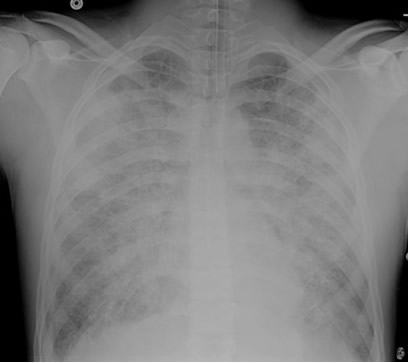

Preintubation CXR for case found here:

(CXR source: http://www.radiology.vcu.edu/programs/residents/quiz/pulm_cotw/PulmonConf/09-03-04/68yM%2008-03-04%20CXR.jpg)